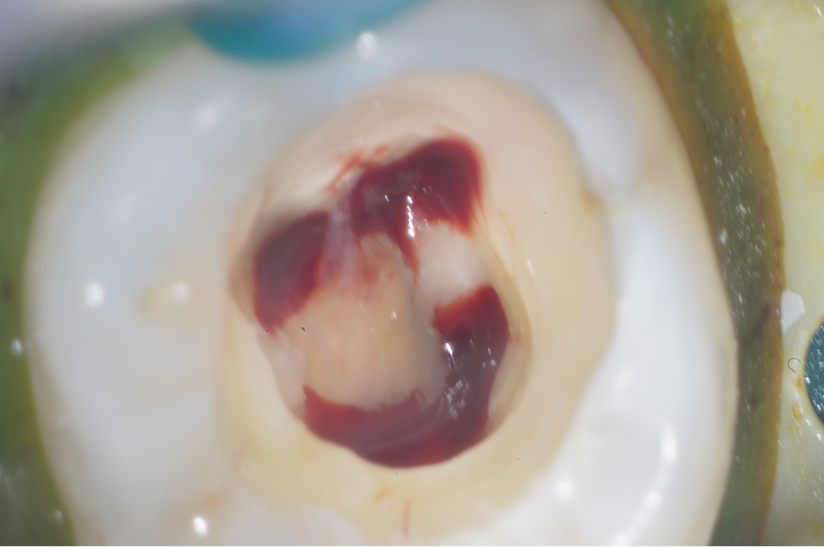

根尖性歯周炎の歯を

再根管治療によって歯を残した症例

タップで写真の拡大ができます。

Before

After

Under Treatment

主訴

抜歯が必要と言われた歯の精査を希望

診断

根尖性歯周炎(根尖吸収、ストリップパーフォレーションを伴う)

治療方針

重度の感染および根管内の損傷が認められる難症例であったが、 歯質の残存量および歯周組織の状態から保存可能と判断した。

歯根破折を疑う所見も認められなかったため、 患者の希望も踏まえ、保存的に再根管治療を行う方針とした。

治療内容

リトリートメント(大臼歯)、MTAセメントによる封鎖、レジンコア

治療期間

約1ヶ月

治療費用

220,000

結果

初診時には根管内に肉芽組織および排膿を認めたが、 感染コントロール後に炎症所見は消失した。

その後MTAセメントにて封鎖を行い、 術後症状は認めず、根尖病変は縮小傾向を示している。

治療の

リスク

根尖病変が完全に消失しない可能性

考察

複数回の根管治療既往があり、根管内は複雑な状態であったが、 適切な感染源の除去と封鎖により良好な経過が得られている。

難症例においては、保存の可否を適切に判断した上で、 精密な処置を行うことが重要である。